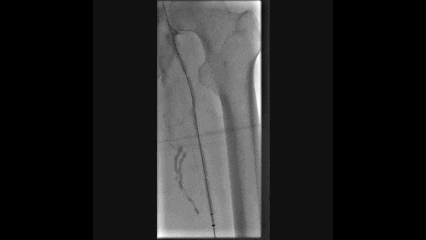

术后造影显示:

左侧股深静脉到左侧髂外及髂总静脉全程通畅

侧支循环消失

形态良好,无明显狭窄,管腔通畅

临床效果:

术后患者左下肢肿胀明显减轻,溃疡疼痛缓解

术后3个月左下肢溃疡完全愈合